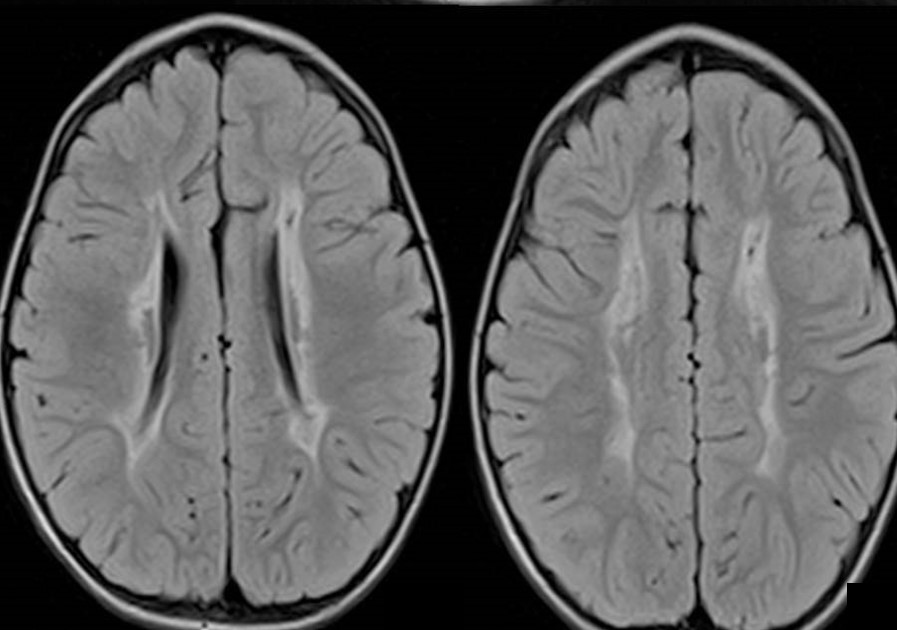

PVL or periventricular leukomalacia is the softening of; the white brain tissue near the ventricles. These ventricles are fluid-filled; they contain CSF or cerebrospinal fluid. This white matter is the inner part of the brain. It is a brain injury characterized by necrosis or coagulation of white matter near the lateral ventricles. The age group susceptible to periventricular leukomalacia is infants and less commonly in fetuses. However, premature infants are at the risk of neonatal encephalopathy, which may later cause this condition. Individuals affected by this leukomalacia generally exhibit other developmental delays or control problems. These problems often develop epilepsy or cerebral palsy later in life. The pathology of the brain was described earlier by many names. Those names were ischemic necrosis, periventricular infarction, brain softening, coagulation necrosis, leukomalacia. It was also known as infarct periventricular white matter or diffuse symmetrical periventricular leukoencephalopathy. This medical condition is now known globally as periventricular leukomalacia.

According to one article, severe periventricular leukomalacia was followed; with the help of ultrasonography. The subsequent brain myelination was assessed; by nuclear magnetic resonance imaging. The results obtained from ultrasonography showed that periventricular leukomalacia took place in four stages.

The first stage of this medical condition was initial congestion, followed later by relative normalization. The third stage then involved the development of cysts and; finally, ventricular enlargement development took place.

All of the observed infants exhibited abnormal neurological signs from 36 weeks. The infants also had; unequivocal indications of cerebral palsy by around 6 to 9 months. Two infants had a normal vision but the third infant seemed cortically blind. NMR results showed an anomaly in the ventricular system and delayed myelination too. The delay in myelination was noticeable in the corticothalamic region. It was the same region with the most extensive lesions observed on ultrasonography. Myelination in the infants was investigated, with a repeatedly performed scan.